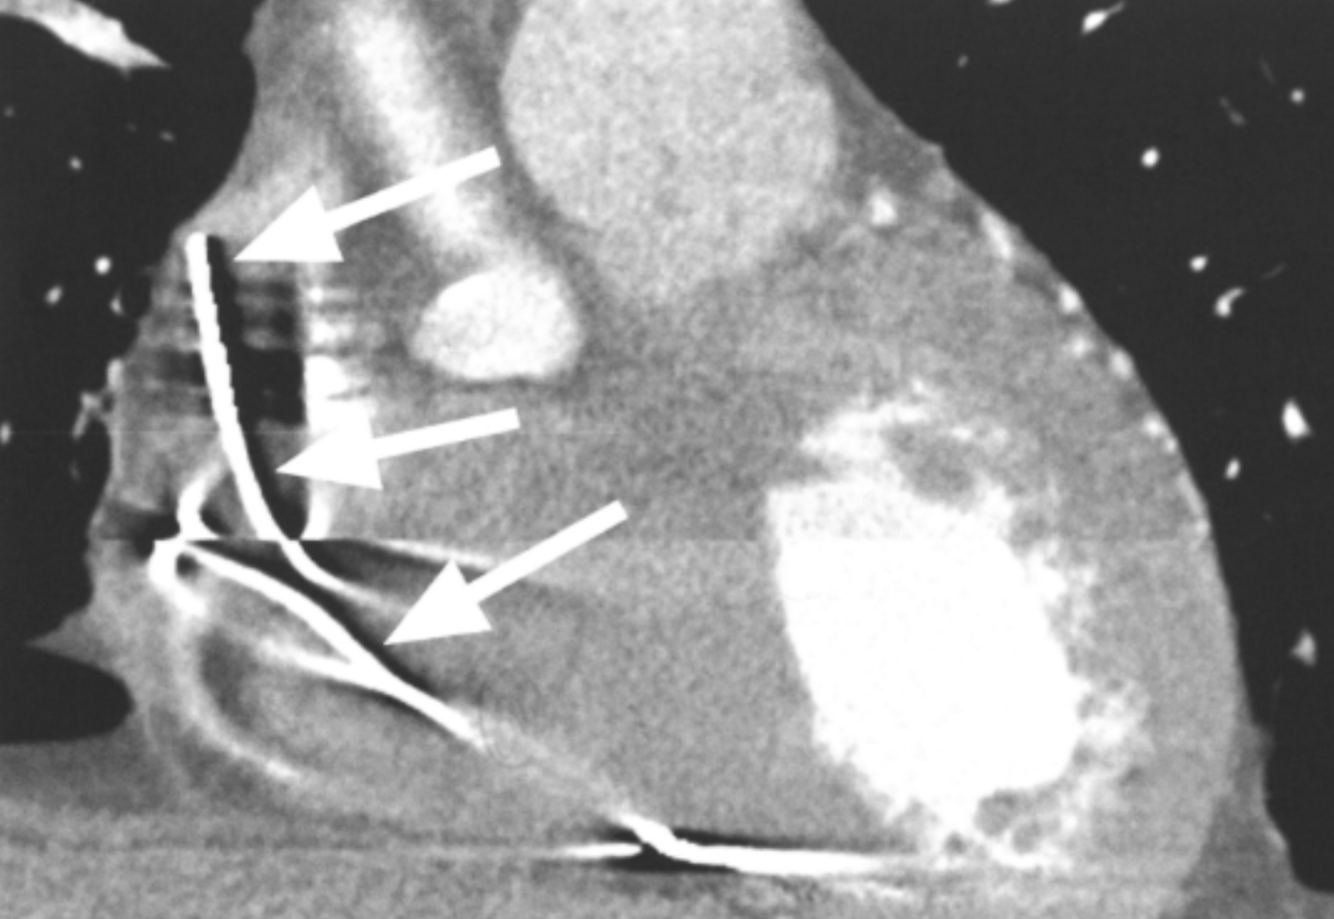

What is the arrow pointing at?

RV pacemaker leads - metal artifacts